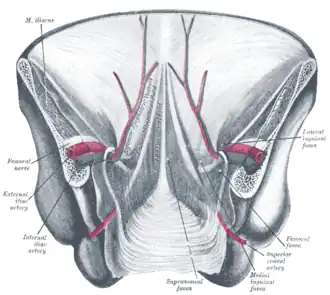

Posterior view of the anterior abdominal wall in its lower half. The peritoneum is in place, and the various cords are shining through.

Posterior view of the anterior abdominal wall in its lower half. The peritoneum is in place, and the various cords are shining through. -